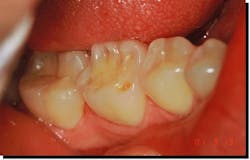

Fatigue is easily recognized in prostheses and restorative materials (figures 3 and 4).

The wavy patterns in amalgam are termed Luder lines or slip bands due to molecules in the alloy rearranging themselves from compressive strain.